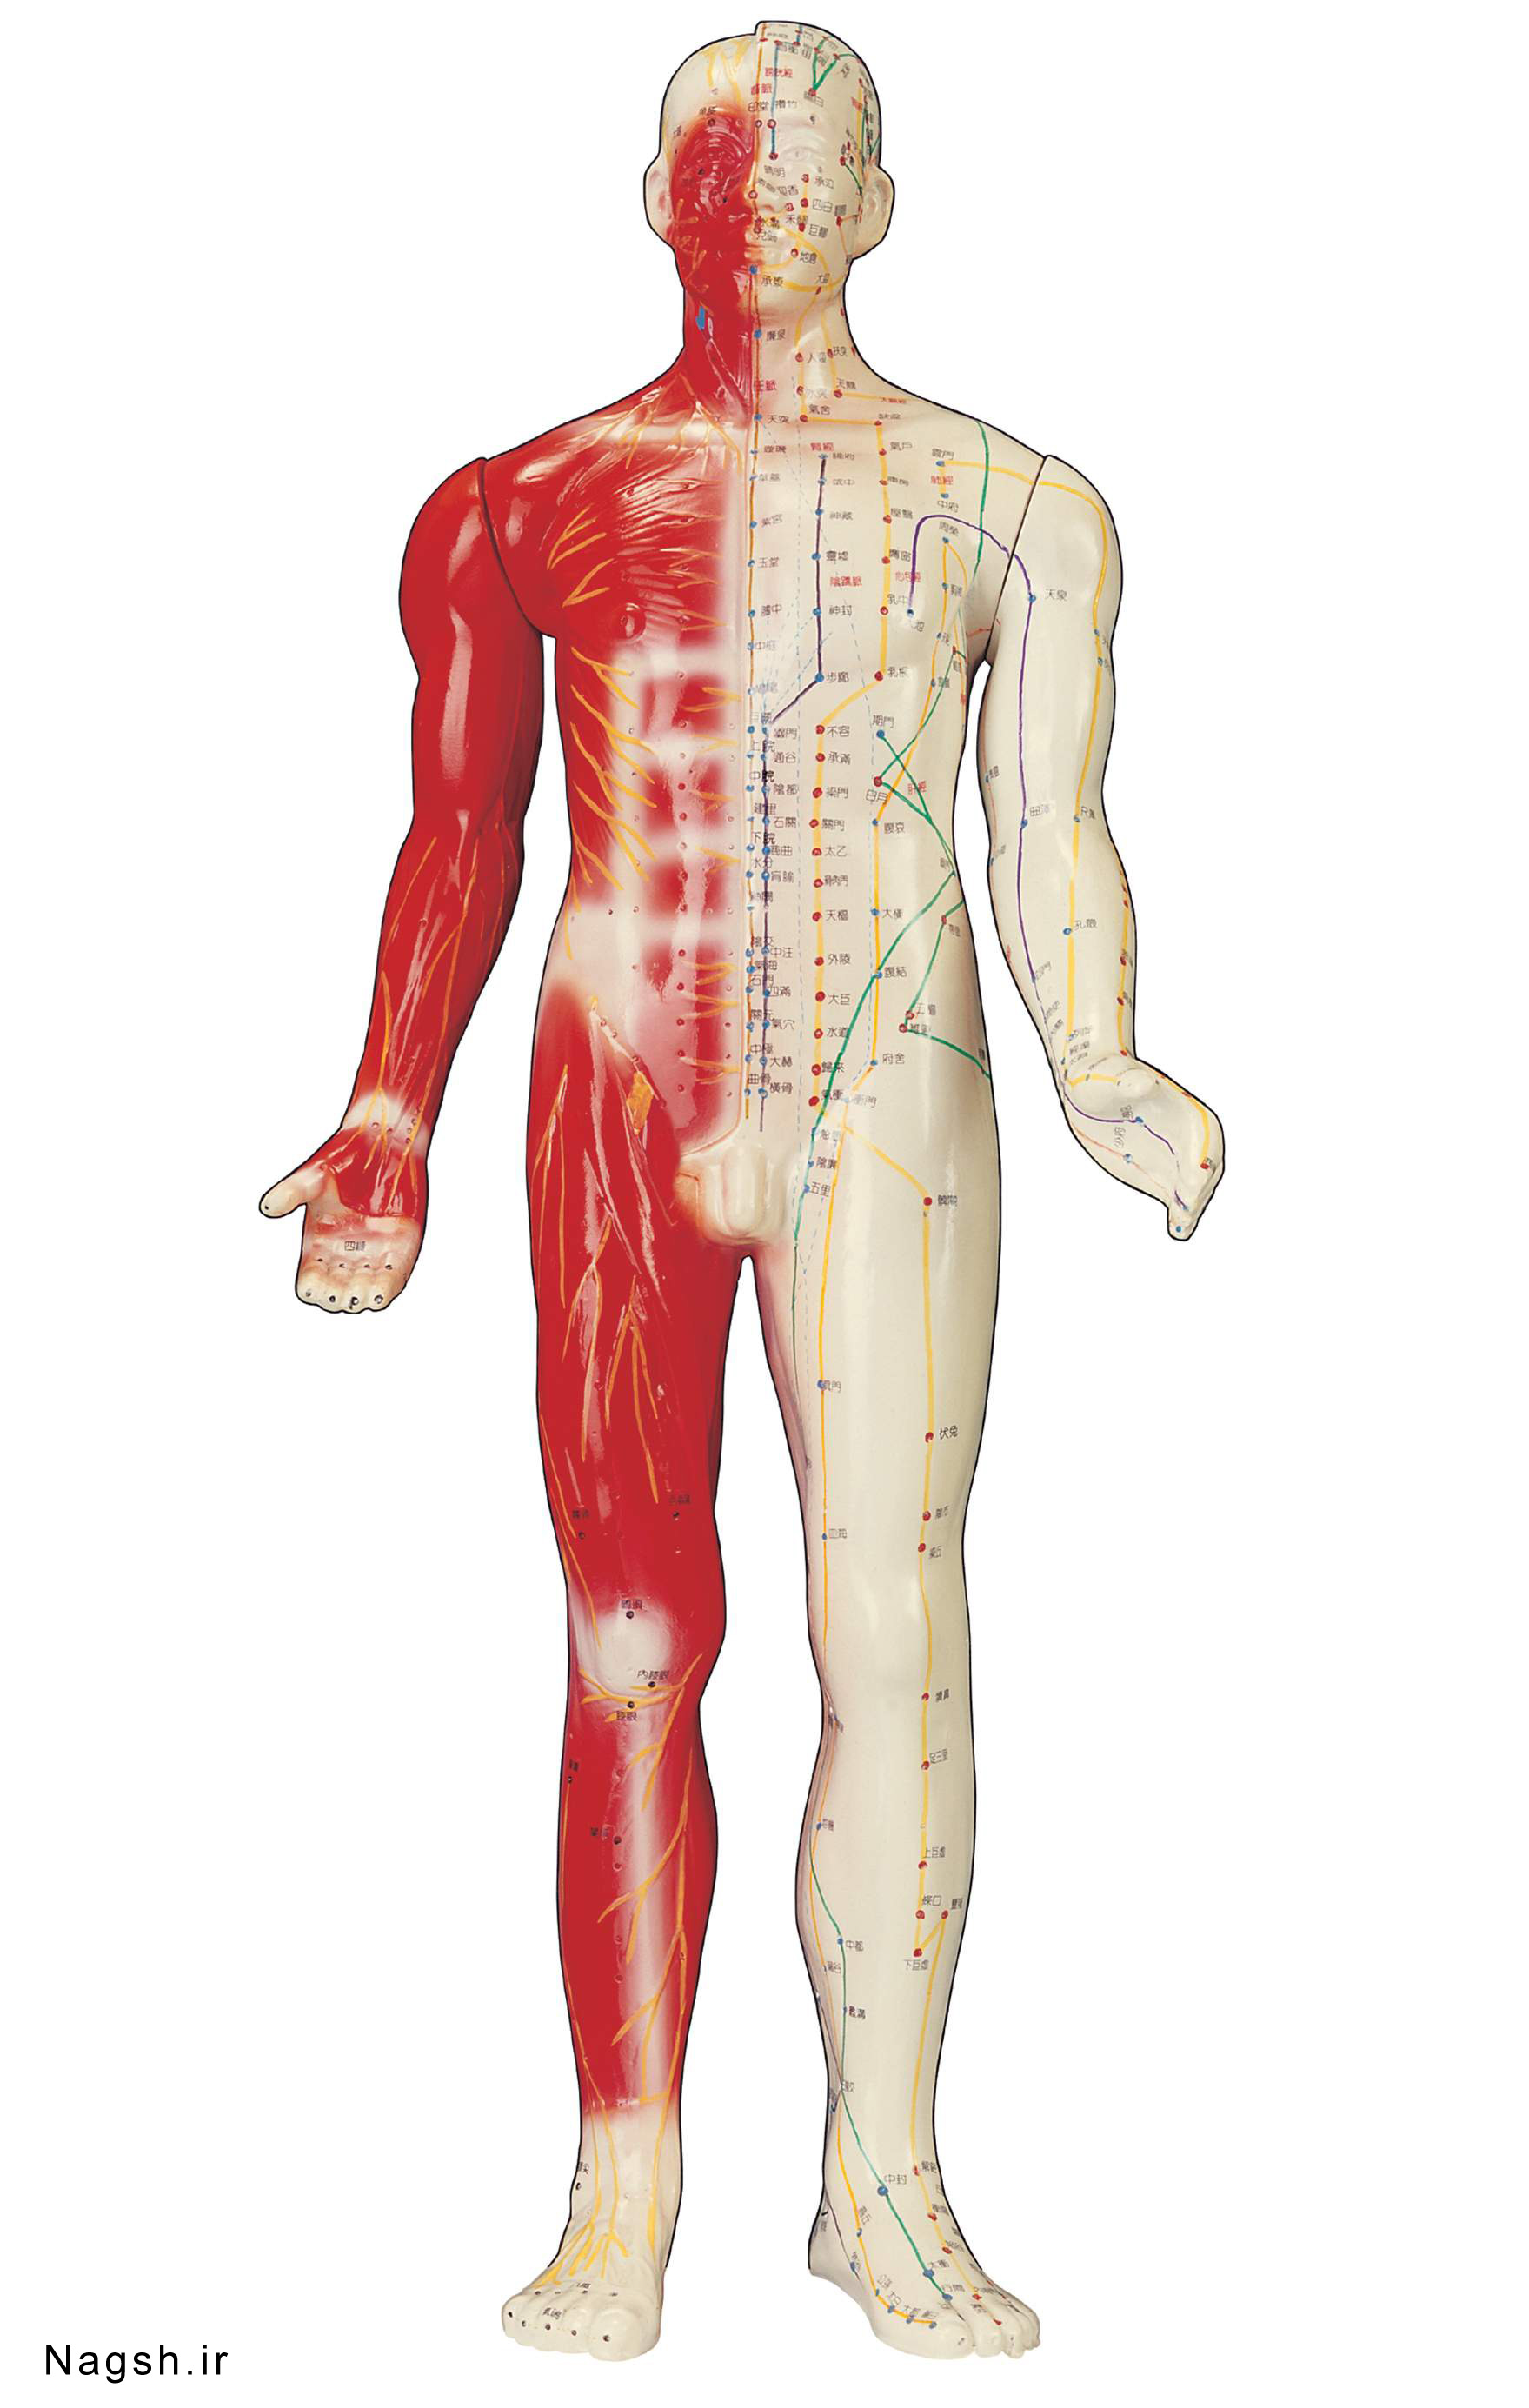

عکس اسکلت بدن انسان با کیفیت. عکس اسکلت عکس اسکلت برای پروفایل عکس اسکلت انسان عکس اسکلت خفن عکس اسکلت بدن انسان با کیفیت عکس اسکلت بدن انسان عکس اسکلت ترسناک عکس اسکلت فانتزی عکس اسکلت فانتزی دخترانه پرچم عکس اسکلت. عکس با کیفیت اسکلت داخلی انسان و درد و گرفتگی در ناحیه استخوان زانو ویژه استفاده در امور تبلیغاتی و تجاری طراحی کاتالوگ بروشور و تراکت با موضوع پزشکی فیزیوتراپی ارتوپد دکتر روماتیسم فیریوتراپ طب فیزیکی. عکس اسکلت بدن انسان زن و مرد آناتومی ساتین 16 سپتامبر 2017. اسکلت داربست بدن است تمام قسمت های بدن روی اسکلت قرارگرفته اند بدن انسان از ۲۰۶ قطعه استخوان تشکیل شده است این استخوان ها طوری با نظم کنار هم قرار گرفته اند که انسان را قادر می سازد حرکات دقیقی داشته باشد.